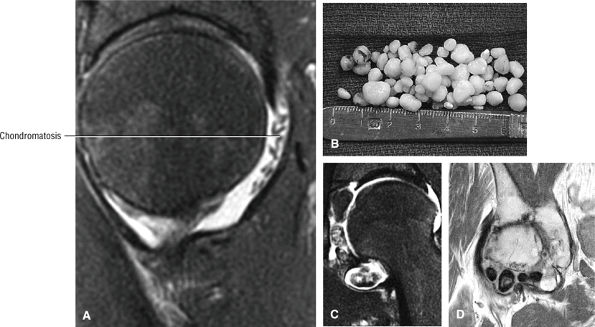

Stage IV: The femoral head undergoes further collapse, leading to articular cartilage destruction and joint space narrowing (Fig. 3.84). Segmental collapse and subchondral fracture may result in pain and disability. Frequently this is the stage at which the patient presents for evaluation, although attention is sometimes sought earlier. Pain may be attributed to increased intraosseous pressure and microfractures.